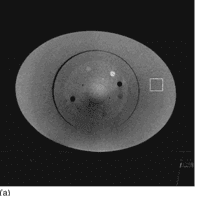

Zhu et al (2009) propuseram um método de supressão de ruído da dispersão que é utilizado nas projeções após a correção da dispersão. Este algoritmo é baseado no uso de Mínimos Quadrados Ponderados Penalizados (MQPP) (penalized weighted least-squares - PWLS) para reduzir o ruído nas imagens reconstruídas, aumentando a relação contraste/ruído (RCR) e trazendo uma melhoria significativa na qualidade da imagem, como mostra na figura 6.

Figura 6 - Imagens reconstruídas do fantoma Catphan © 600 anel de corpo oval.

(a)  Sem correção da dispersão e sem supressão de ruído; (b) Com correção da dispersão, porém sem supressão de ruído; (c) Com correção da dispersão usando o algoritmo de supressão de ruído proposto; Fonte: (Zhu et al.,2009)